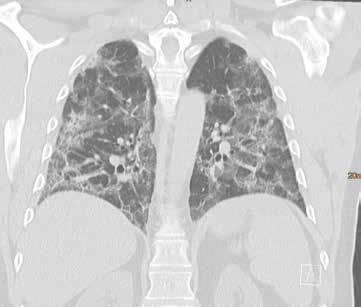

Fall 3:

Thorax-CT im Rahmen einer Lungenkrebsfrüherkennungsstudie. Die Voruntersuchung lag als externe kontrastmittelgestützte Thorax-CT vor. Bei der dosisoptimierten Low-Dose-CT liegt die Strahlenexposition nur noch im Bereich von zwei konventionellen Röntgenaufnahmen des Thorax, die Bildqualität ist für die Fragestellung nach Herdbefunden aber dennoch eindeutig ausreichend, selbst interstitielle Lungenveränderungen lassen sich hier noch beurteilen.

Prof. Dr. med. Johannes Weßling Zentrum für Radiologie, Neuroradiologie und Nuklearmedizin Abb. 3 a: kontrastmittelgestützte Thorax-CT, externe Untersuchung; DLP 216,0 mGy × cm / 3,9 mSv. Abb. 3 b: dosisoptimierte Low-Dose-Thorax-CT, Canon Aquilion Prime SP, Rekonstruktion: AiCE; DLP 13,9 mGy × cm / 0,25 mSv.